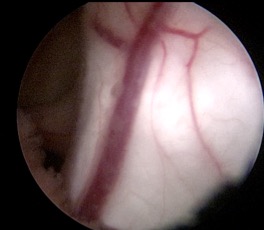

le plus souvent, on réalise en urgence une ventriculocisternostomie endoscopique ; ceci permet de mettre le patient à l’abri du risque d’engagement et de lésion des nerfs optiques, mais ne résout pas le problème de la compression du tronc cérébral.

l’endoscopie reste souvent possible malgré la présence de métastases méningées car le blocage est en général localisé au niveau de l’incisure tentorielle ; elle est même souvent possible en cas de métastase de l’infundibulum tubérien.

on obtient des échantillons de LCS pour la recherche de cellules tumorales, on constate parfois une dissémination tumorale non visible radiologiquement, et on peut parfois réaliser des biopsies endoscopiques, mais celles-ci permettent rarement d’établir le diagnostic et de se passer d’un abord direct de la tumeur.